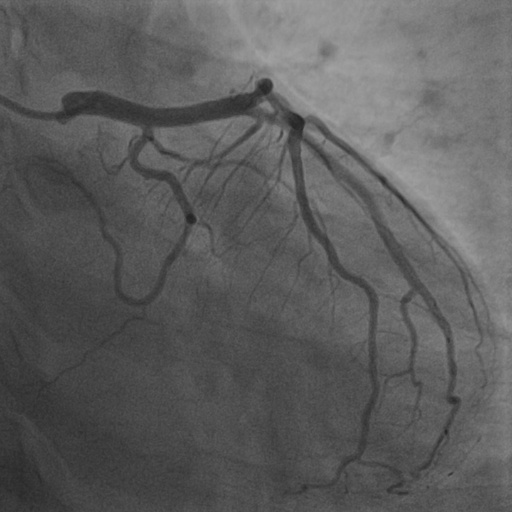

4.1 XACV Dataset

We collect 111 complete records of coronary artery X-ray videos, encompassing the injection, flow through the blood vessels around the heart, and dissipation of the contrast agent. Subsequently, we establish the XACV (X-ray Angiography Coronary Video) dataset. Each video consists of varying numbers of high-resolution coronary artery X-ray images. We invite experienced radiologists to annotate the vascular regions, focusing on one or two frames where the contrast agent is most prominent in each video. The XCAD dataset contains only a single image, and the CADICA video dataset does not provide corresponding ground truth. Therefore, in the following experiments, we conduct all the analyses on our collected XACV dataset and the corresponding GT for each sequence. In Figure 5, we show that compared to other publicly available datasets, XCAD [33] and CADICA [19], our dataset exhibits finer annotations in the vascular regions, providing an advantage for future related tasks. The development and use of our dataset have been approved by our institution’s IRB.